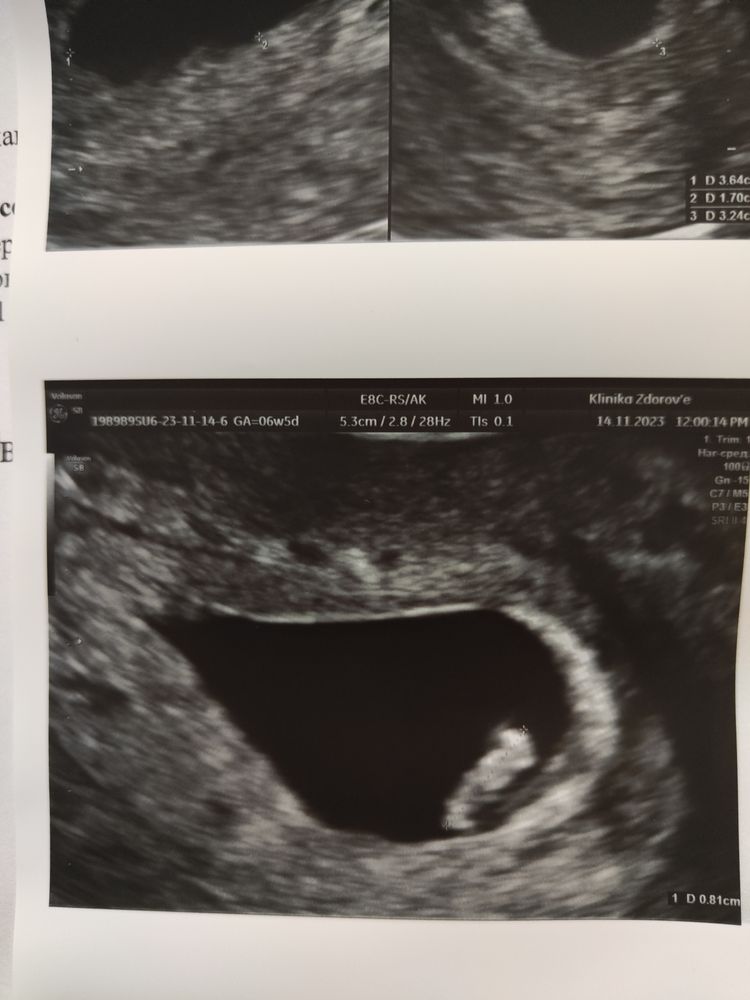

6+5) нашли нашу крошку😍

Я ходила ровно в 6,0 неделек по мес, ктр 6.9 и чсс 118 Но я ходила к лучшему специалисту в городе, к КМН. Он сказал все хорошо. Затем ходила в 7.6 нед , ктр уже 2см и чсс 170

Маленькая креветочка😍 Пусть растёт здоровой! 🙏❤

Катюнечка Солнышко, а я головастиком назвала. Новости хорошие какие. То девчонки с полосатыми тестами одна за другой. Теперь вот на узи увидели.

Катюнечка Солнышко, 🥰😘моя крошка) через недельку ещё глянем на нее